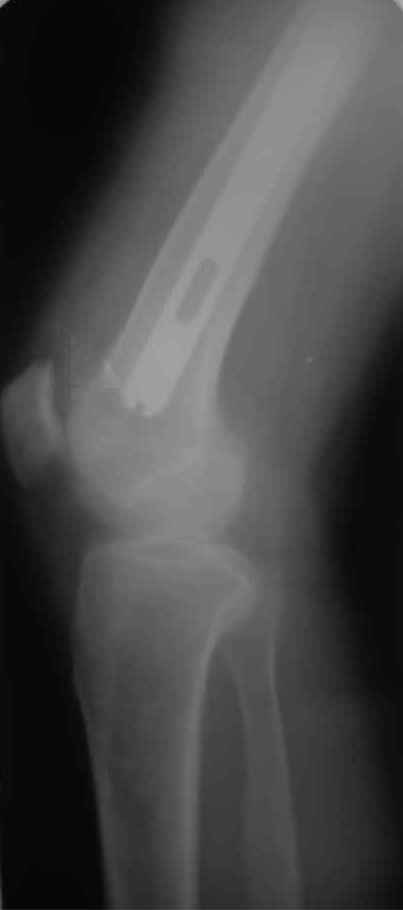

А нельзя ли увидеть и профиль бедра на всем протяжении, т.е. и весь протез, и весь стержень? И фас бы с коленом.

новые снимки

Пациента удалось осмотреть недавно. Достигнутый результат сохраняется. Перелом бедра сросся. Конечность опорная и безболезненная, ходит без трости. Ножка, похоже, реинтегрировалась, как и надеялись. Снимки и фото в приложении. Комментарии приветствуются.

Надо ли что-то делать дальше, как полагаете? Убрать винты? Убрать "удлинитель ножки"? Или оставить все, как есть? Спасибо заранее.